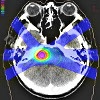

Контрастирование при МРТ

Магнитно-резонансная томография с контрастным усилением включает томографию интересующей анатомической зоны после введения парамагнитного вещества. В отличие от нативного исследования, контрастная магнитно-резонансная томография позволяет более точно визуализировать патологические очаги в органах и их пределах для проведения дифференциальной диагностики заболеваний органического генеза. Препараты на основе гадолиния (омнискан, магневист, гадовист ) И оксид железа (гастромарк, абдоскан ) Используются в качестве контрастного вещества для магнитно-резонансной томографии. Контрастность дается до исследования, внутривенно (струйно, болюсно) или орально; Доза рассчитывается исходя из веса пациента. Магнитно-резонансные контрастные агенты имеют меньшую токсичность и аллергенность по сравнению с аналогичными рентгеновскими и компьютерными томографическими препаратами, поэтому имеют меньше противопоказаний к применению.